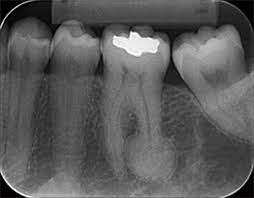

Pulpitis Reversible

La pulpitis reversible es una inflamación leve de la pulpa dental, generalmente causada por caries o una lesión menor.

Los pacientes suelen experimentar sensibilidad al frío o al calor, pero el dolor desaparece rápidamente.

Si se trata adecuadamente, la pulpa puede sanar sin complicaciones. Es importante acudir al dentista para evitar que progrese a una pulpitis irreversible.